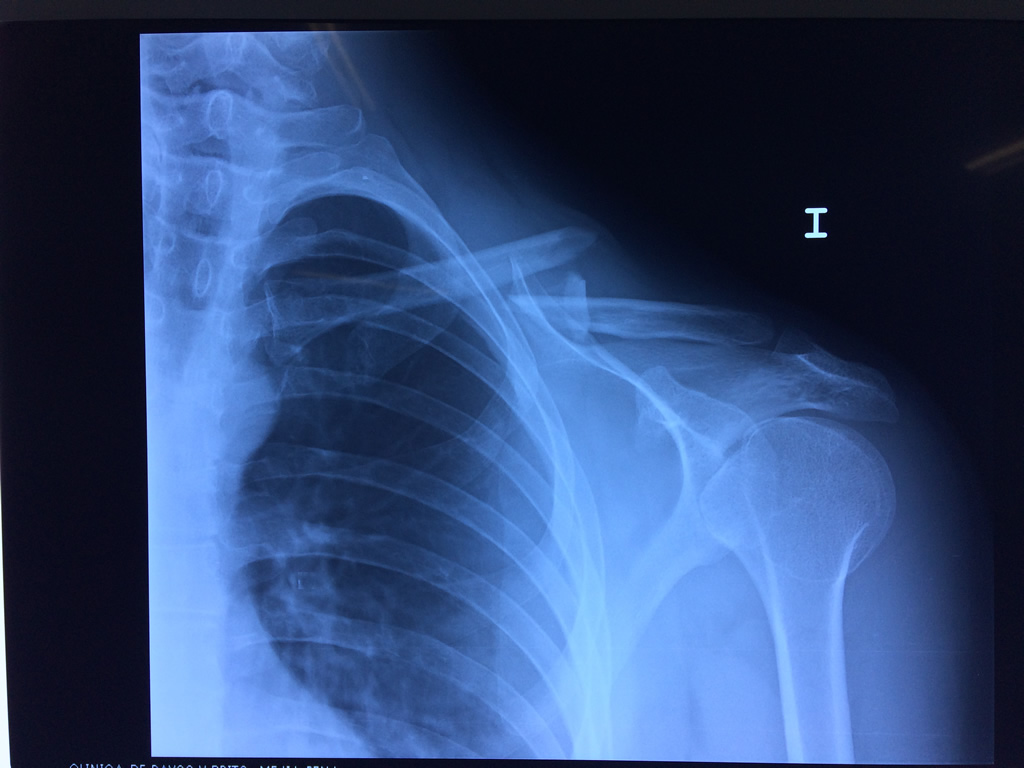

Calcaneo - Clavícula

La clavícula es un hueso largo, con forma de "S" itálica, situado en la parte anterosuperior del tórax. Junto con la escápula forman la cintura escapular. Se puede palpar por toda su longitud y se extiende del esternón al acromion de la escápula, siguiendo una dirección oblicua lateral y posterior.